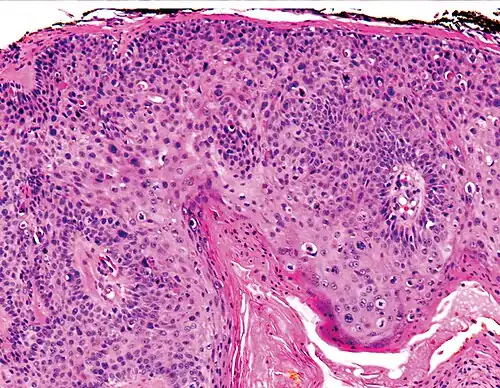

In situ disease

Bowen's disease is essentially equivalent to and used interchangeably with cSCC in situ, when not having invaded through the basement membrane.[12] Depending on source, it is classified as precancerous[13] or cSCC in situ (technically cancerous but non-invasive).[48][49] In cSCC in situ (Bowen's disease), atypical squamous cells proliferate through the whole thickness of the epidermis.[12] The entire tumor is confined to the epidermis and does not invade into the dermis.[12] The cells are often highly atypical under the microscope, and may look more unusual than the cells of some invasive squamous-cell carcinomas.[12]

cSCC in situ, high magnification, demonstrating an intact basement membrane.[12] -

cSCC in situ -